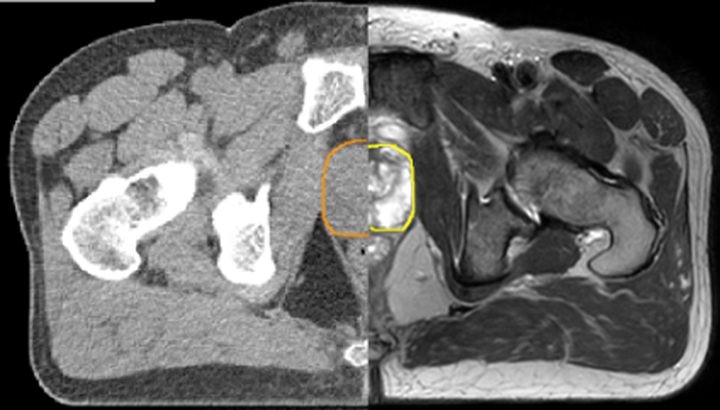

Our innovative MRCAT (MR for Calculating ATtenuation) clinical applications lets you plan radiation therapy using MRI as primary imaging modality. Within just one, fast MR exam, MRCAT provides both excellent soft-tissue contrast for target and OAR delineation and CT-like density information for dose calculations.

This not only extends the benefits of MRI’s excellent soft-tissue contrast to radiotherapy planning, but it also eliminates arduous, error-prone CT-MRI registration from the process, reducing uncertainties and complexity.

Explore clinical cases that demonstrate the use of MRI for RT planning.